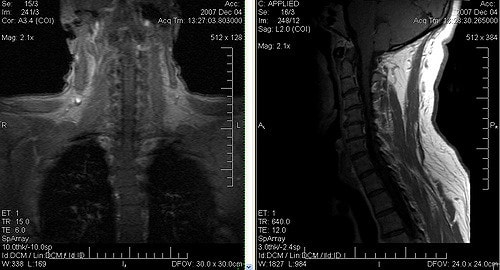

Иногда болит шея и затылок, а причина не установлена. В этом случае, комплексное исследование сосудов и магниторезонансная томография дадут чёткую клиническую картину и подтверждают мигрень. Заболевание может охватывать не только голову, но и шею.

- МРТ шеи и головы.